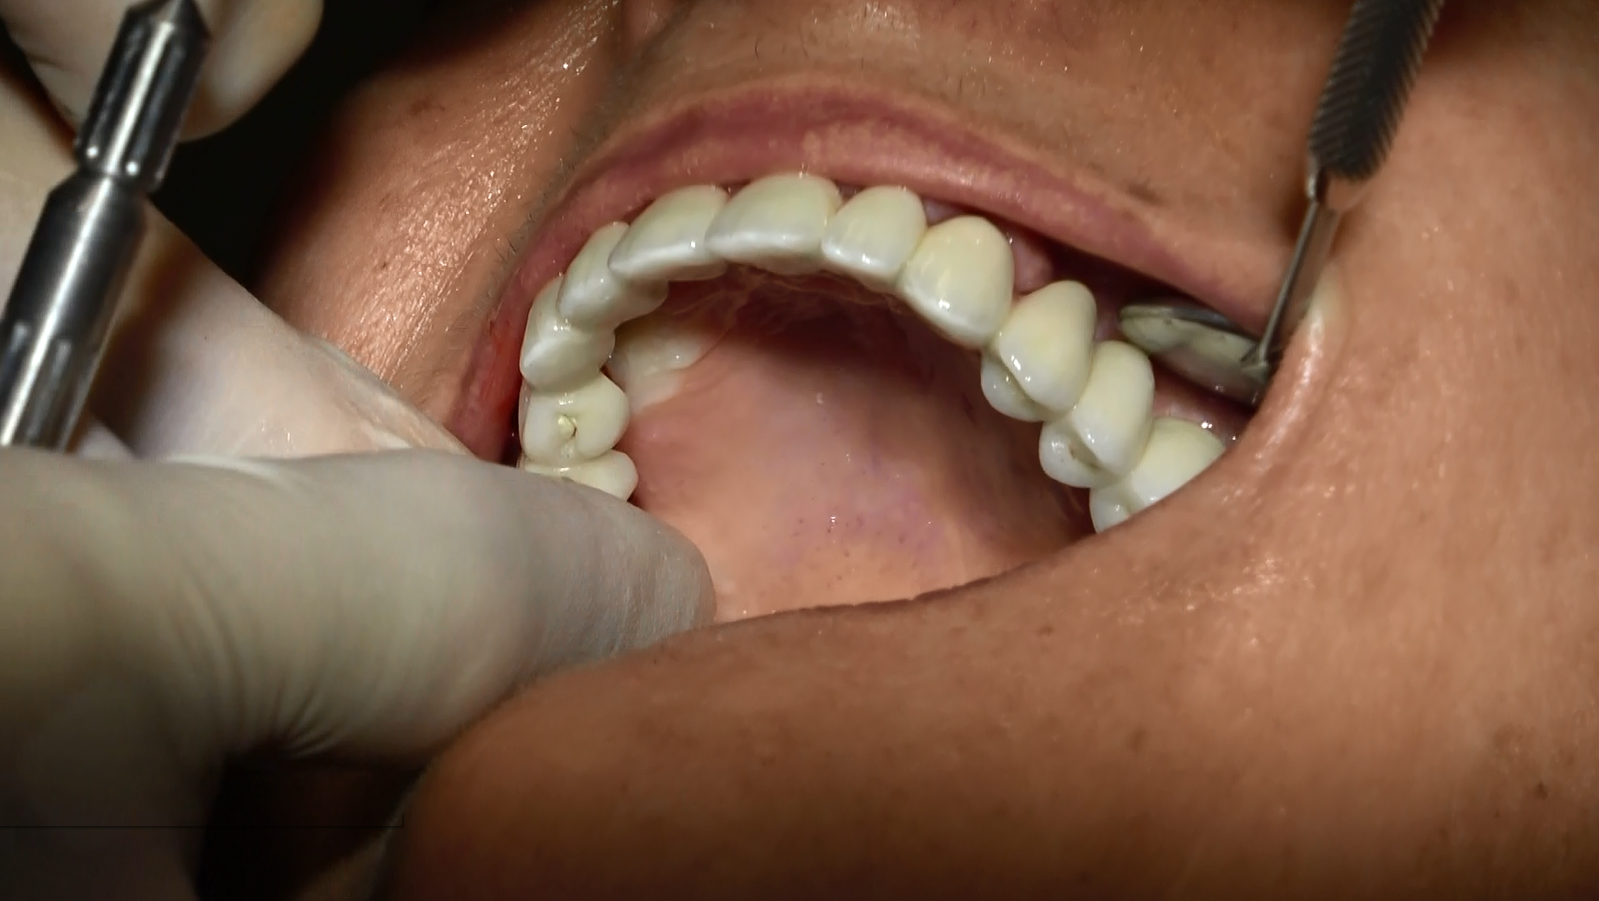

- Posizionamento degli Impianti Sottoperiostei: Gli impianti sono stati posizionati direttamente sulla superficie dell’osso mascellare, garantendo stabilità e supporto adeguati.

- Carico Immediato: Grazie all’implantologia sottoperiostea, il paziente ha beneficiato del carico immediato, ottenendo denti fissi funzionali in un tempo incredibilmente breve.

Il paziente, dopo un periodo di recupero relativamente breve, ha ripristinato la funzionalità e l’estetica del sorriso. Questo caso dimostra come l’implantologia sottoperiostea possa essere una soluzione efficace anche per pazienti con atrofia ossea estrema, offrendo risultati duraturi e soddisfacenti.